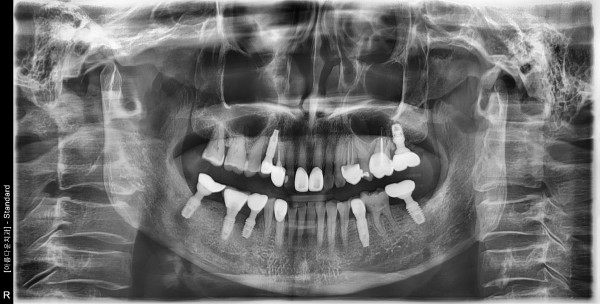

60대 여성 임플란트 식립

e42e986bdfcf919f5813591835ea9a60_1759110